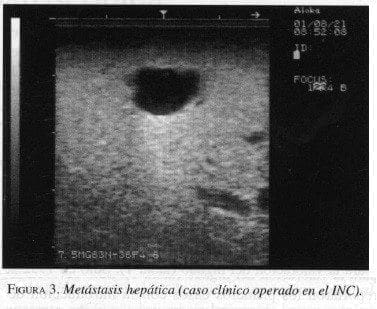

Diferentes publicaciones sobre la evaluación laparoscópica con ultrasonido antes de definir la laparotomía en casos de cáncer gastrointestinal describen su utilidad, en la reducción del número de laparotomías en casos de irresecabilidad de las lesiones. Durup y Hovendal (7), en Dinamarca, presentaron su experiencia en la evaluación del ultrasonido en tumores de hígado, esófago, estómago y páncreas; en el primero fue de más fácil desarrollo. A menudo las lesiones malignas se visualizaron como lesiones oscuras (hipoecoicas), redondeadas, inmersas en el parénquima hepático, en relación con conductos biliares y vasos sanguíneos claramente distinguibles (figura 3). La laparoscopia demostró factores que precluían el intento de una resección en el 46% de los pacientes; adicionalmente el ultrasonido laparoscópico reveló lesiones no visualizadas previamente en un 33% de los mismos pacientes.